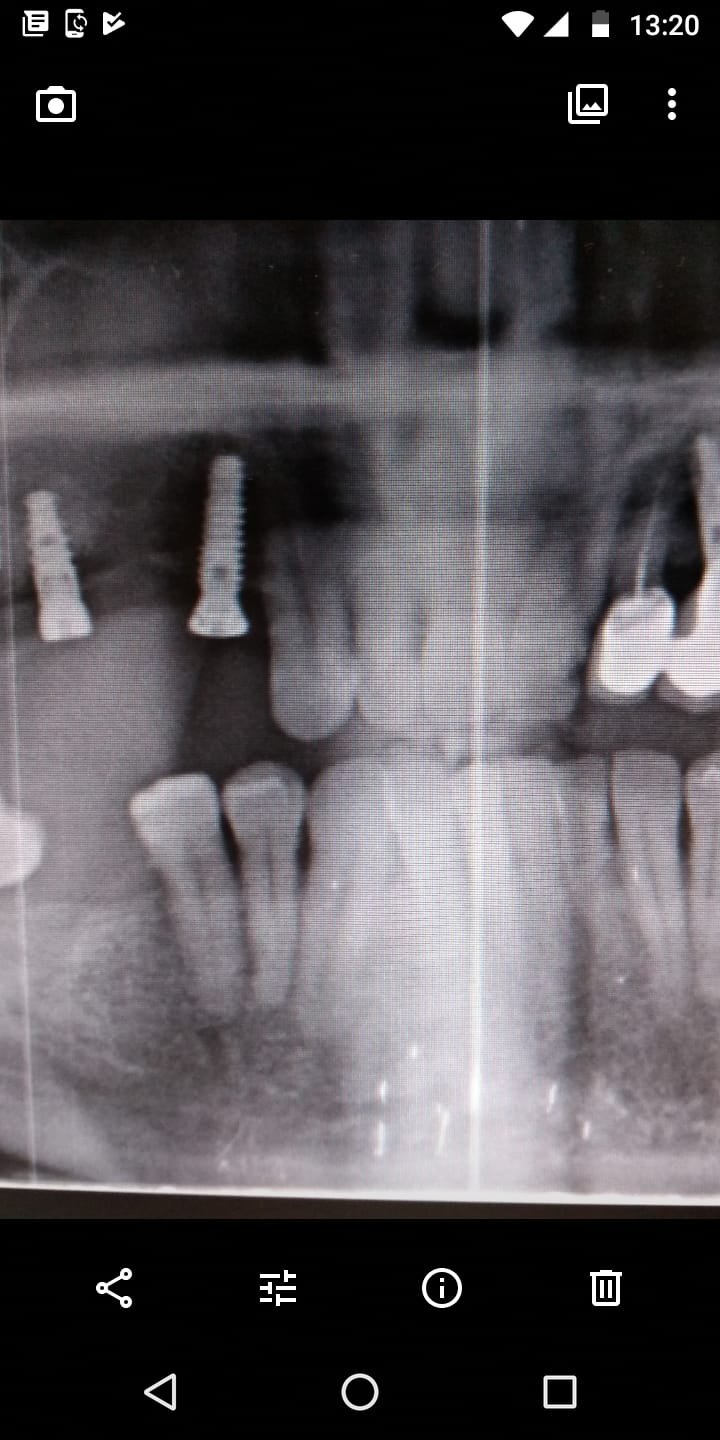

Buenos días. Muchas gracias por vuestra web, es muy interesante. Me estreno por fin en ella tras varias recomendaciones de amigos. Os envío la ortopantomografía de 3 implantes de mandíbula [...]